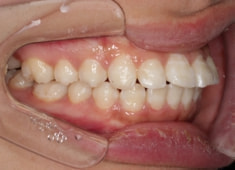

治療前

治療後(1年12ヶ月後)